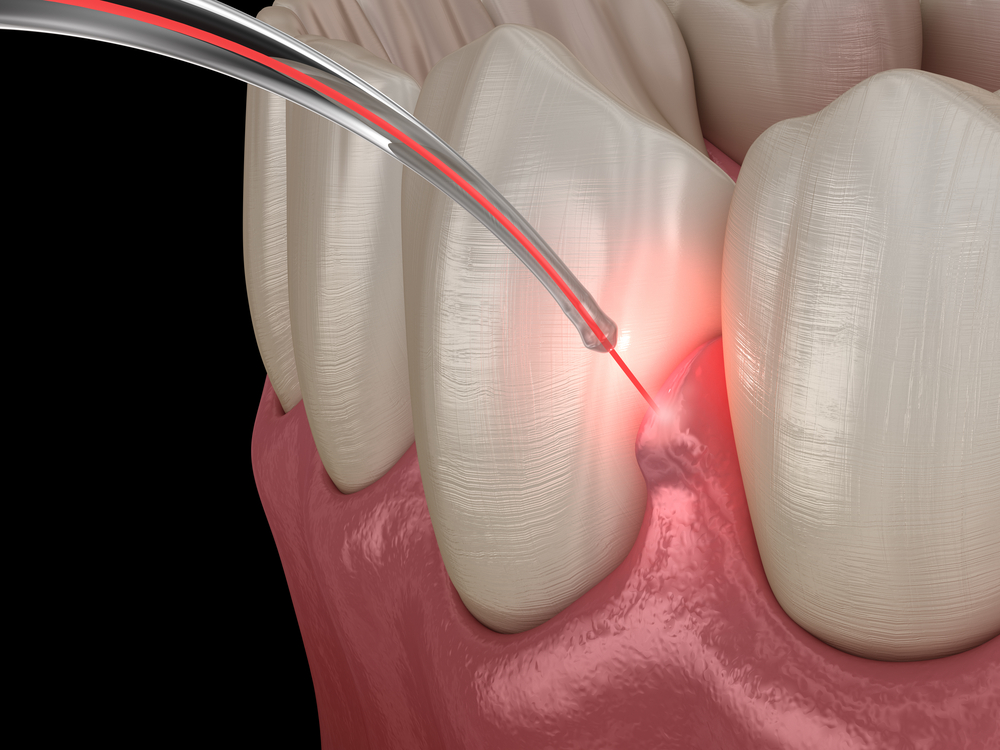

Professional teeth cleaning to maintain oral hygiene and prevent dental problems.

Our Gallery